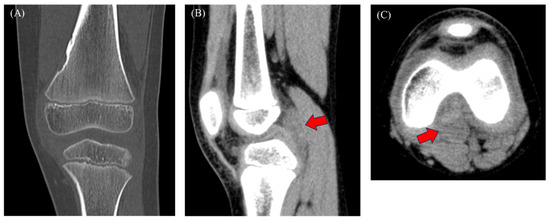

This report describes a rare case of a pediatric tenosynovial giant cell tumor (TSGCT) with a delayed diagnosis. A 9-year-old boy presented with a 3-month history of knee pain and swelling, initially attributed to a femoral non-ossifying fibroma and arthritis based on computed [...] Read more.

This report describes a rare case of a pediatric tenosynovial giant cell tumor (TSGCT) with a delayed diagnosis. A 9-year-old boy presented with a 3-month history of knee pain and swelling, initially attributed to a femoral non-ossifying fibroma and arthritis based on computed tomography findings and slightly elevated C-reactive protein levels. The symptoms persisted despite medical treatment. Magnetic resonance imaging (MRI) revealed a tumor in the posterior compartment. He underwent surgery, and the pathology confirmed the diagnosis of localized TSGCT. Six months postoperatively, the patient remained asymptomatic. Pediatric knee pain is a complex symptom associated with inflammatory conditions and benign and malignant tumors. Benign tumors, as in this case, can be misdiagnosed as arthritis, delaying diagnosis and treatment. MRI is recommended in cases involving symptom persistence. However, histopathological, immunohistochemical, and morphological examinations are crucial for definitive diagnosis, particularly when the imaging findings are inconclusive. Full article